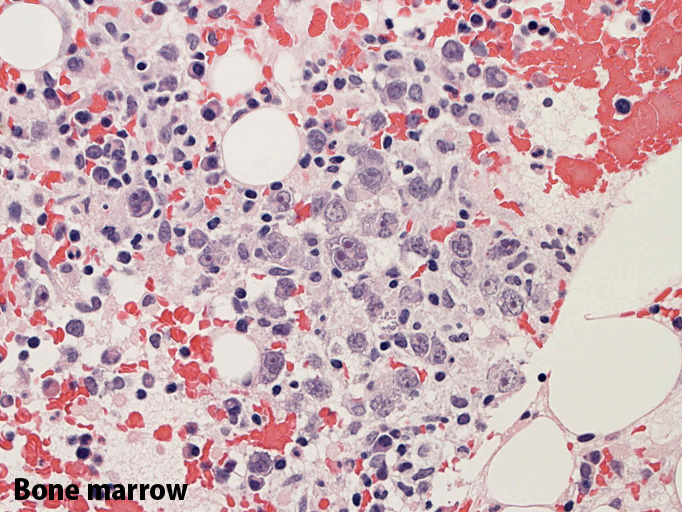

骨髄;細動脈内のみに腫瘍細胞が認められた。類洞や髄内での増殖は見られなかった。

(骨髄穿刺吸引では発見できなかった原因のようです。骨髄生検で細動脈がとれないと診断に結びつかなかったでしょう。)

骨髄の組織所見